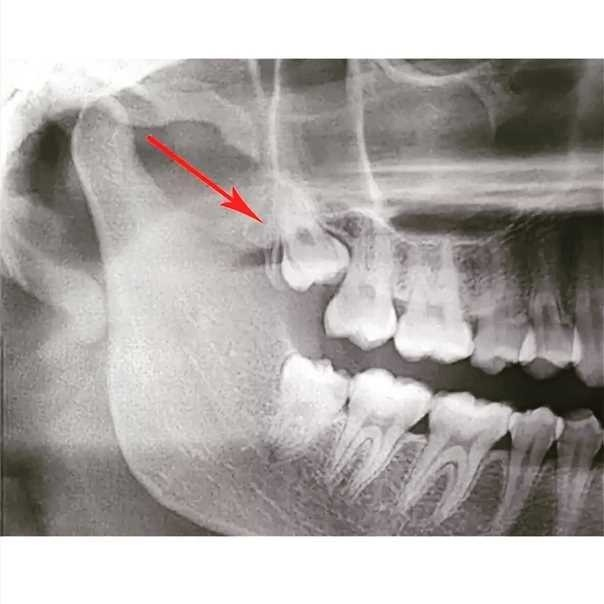

Обзор на удаление зуба мудрости в БЕСПЛАТНОЙ государственной поликлинике. И преимущество перед платными.

Вот в этом и преимущество, ибо если вы пойдете в частную, то в прайсе будет написано: удаление зуба мудрости 7тыс. При звонке скажут, да 7 тысяч приходите. По приходу вам скажут сначала платный осмотр 2к. Потом снимок 1.5 к. Удаление зуба 7к. Наложение шва 2к. И дальше дальше, будут просто сосать бабки из вас.